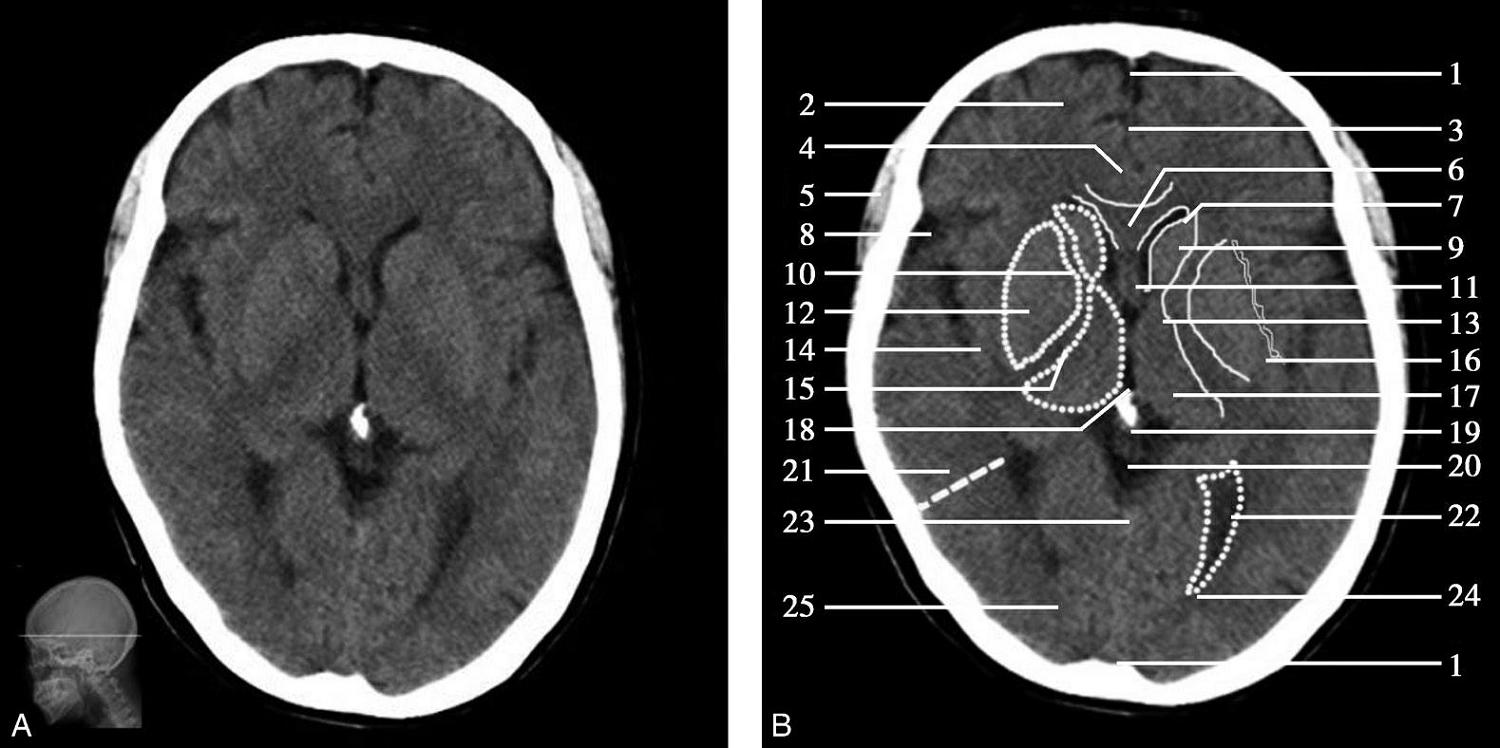

图1-2-24 松果体层面

A.横断面;B.横断面标注

1.上矢状窦;2.额叶;3.大脑镰;4.扣带回;5.颞肌;6.胼胝体膝部;7.侧脑室前角;8.外侧裂池;9.尾状核头部;10.内囊前肢;11.透明隔;12.豆状核;13.内囊膝部;14.岛叶;15.内囊后肢;16.外囊;17.丘脑;18.第三脑室;19.松果体(钙化);20.大脑内静脉;21.颞叶;22.侧脑室三角区;23.直窦;24.侧脑室后角;25.枕叶

双侧侧脑室前角呈弯角状,由胼胝体膝、透明隔、穹窿柱及尾状核头围成。侧脑室前角经室间孔与位于中线的第三脑室相通。第三脑室两侧为背侧丘脑,后界为松果体。松果体肿瘤常发生于此(图1-2-27)。尾状核头、背侧丘脑与豆状核之间为内囊,内囊分为前肢、膝部和后肢等三部分。豆状核呈三角形,外侧大部为壳核,内侧部分为苍白球。外囊居壳核的外侧,其外侧依次为屏状核、最外囊、岛叶及外侧裂池。外侧裂池弯曲狭长,内有大脑中动脉走行,外侧有颞叶。松果体后方为大脑大静脉池,大脑大静脉池外侧有侧脑室三角区,其后部伸入枕叶,称后角。侧脑室三角区为后角与下角的移行处,为侧脑室最宽处。由侧脑室三角区向外延伸的虚线可作为横断面颞叶和枕叶的大致分界线。

松果体、苍白球在成人期常出现钙化,属生理性钙化,一般无病理意义。需注意勿误诊为出血灶,尤其是单侧苍白球钙化时(图1-2-28)。